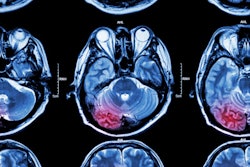

Dementia MRI with segmentation. Image and caption courtesy of Icometrix.The company noted that it's collaborating with Kathleen Poston, MD, a professor of neurology and neurological sciences at Stanford Medicine. She heads a research project evaluating volumetric patterns of brain MRI scans and correlating these to corresponding clinical scores for motor and cognitive function, according to Icometrix.

Poston presented initial findings at the recent 2023 Alzheimer's and Parkinson's Disease Conference, showing that regional brain volumetry assessment can serve as an important biomarker in prediction and differentiation of PD patients at risk for motor and/or cognitive disability progression.